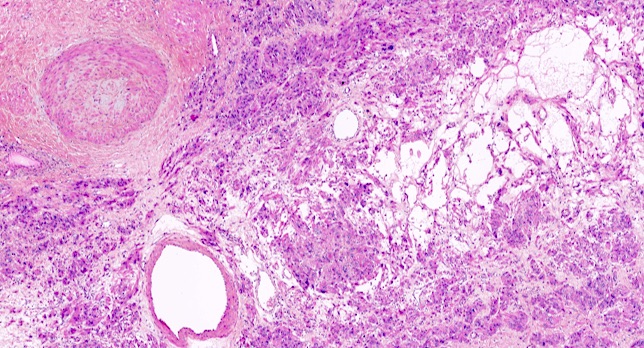

Microscopic (histologic) description

- Conventional / usual leiomyoma (spindle):

- Well defined borders

- Normocellular

- Intersecting fascicles of monotonous spindle cells with indistinct borders, eosinophilic cytoplasm, cigar shaped nuclei (with tapered ends) and small nucleoli

- Atypia: absent or mild

- Mitoses: rare (in general < 5/10 high power fields)

- Blood vessels with thick walls

- With or without infarct type necrosis, hyalinization, calcification, cystic change

- Subtypes:

- Cellular

- Increased cellularity (more cellular than background myometrium)

- Scant cytoplasm without increased mitotic activity and atypia

- May have irregular borders

- Hydropic:

- Tumor cells separated by watery or eosinophilic and proteinaceous fluid, resulting in a trabecular, nested architecture

Microscopic (histologic) images

Contributed by Sabrina Croce, M.D., Ph.D., Kristina Doytcheva, M.D., Jennifer A. Bennett, M.D. (Case #508) and @Andrew_Fltv on Twitter